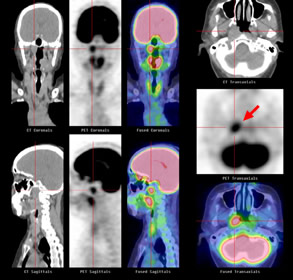

Ct検査よりがん組織と正常組織の区別が明確でct検査とは異なる情報からがんの深さや広がりリンパ節への転移の有無を調べます 7超音波エコー検査 首の表面から超音波をあ てそのはね返りをモニターで見ながら確認. 下咽頭癌の進展範囲を読影する際のチェックポイント 腫瘍の最大径 喉頭への進展の有無 軟骨浸潤の有無 上下方向への進展範囲の決定中咽頭頸部食道 軟部組織浸潤の有無特に梨状癌 梨状窩尖部への進展の有無.

9回目pet ct Mri検査と血糖値 仕事をしながら中咽頭癌と闘う美容